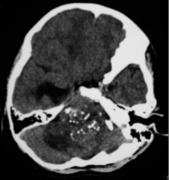

脑膜瘤

脑膜瘤严重吗?脑膜瘤事实解读

脑膜瘤是脑膜上的肿瘤。头骨保护大脑。在头骨内部,覆盖大脑...